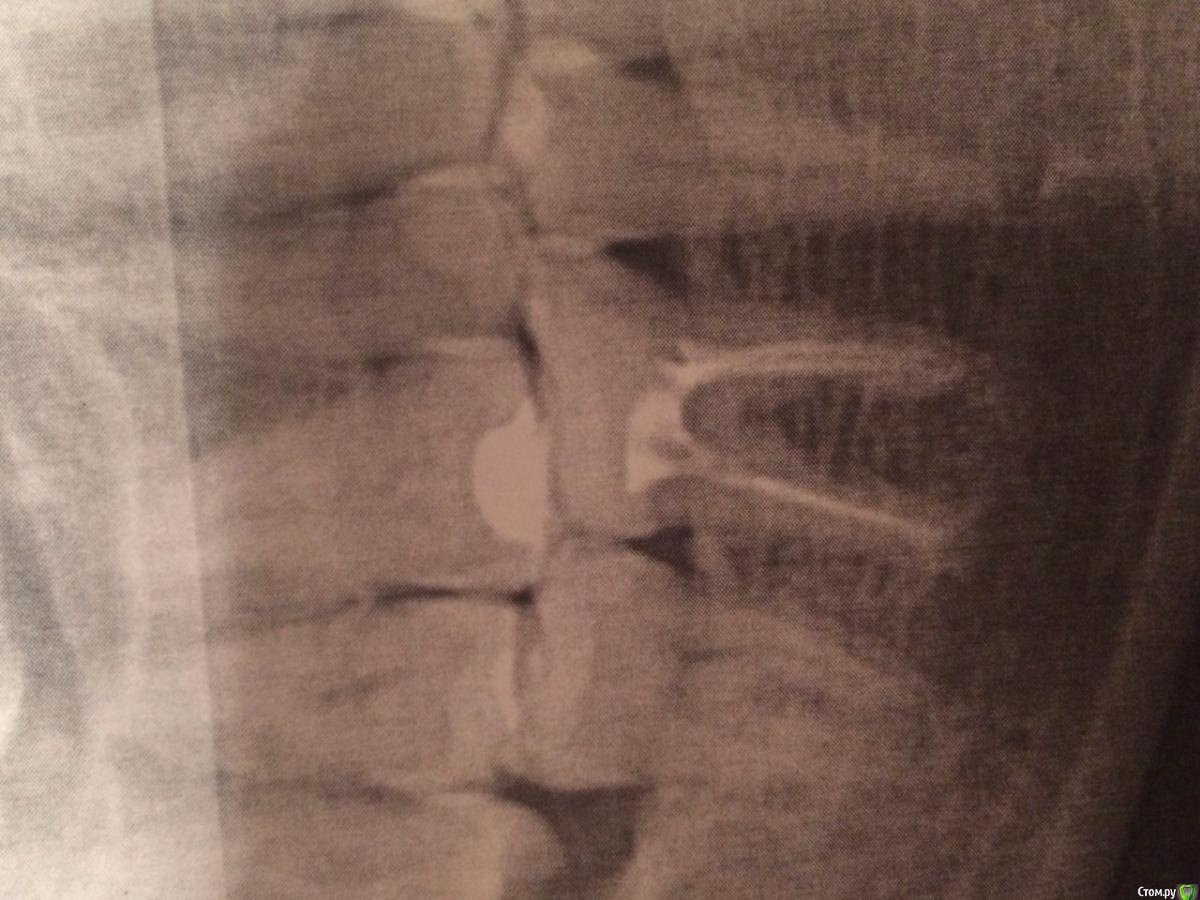

Клематис Опубликовано 18 августа, 2015 Автор Поделиться Опубликовано 18 августа, 2015 Ссылка на комментарий

diesel87 Опубликовано 18 августа, 2015 Поделиться Опубликовано 18 августа, 2015 Это метапекс? А после постоянной обтурации? Ссылка на комментарий

Клематис Опубликовано 18 августа, 2015 Автор Поделиться Опубликовано 18 августа, 2015 Это уже постоянная обтурация. Извините за качество снимка. По снимку ощущение что не допломбировала. Хотя работала с апекслокатором, линейкой. Прицельный во время обработки не было возможности сделать, т к он сейчас у нас в ремонте((( Ссылка на комментарий

elenasyp Опубликовано 19 августа, 2015 Поделиться Опубликовано 19 августа, 2015 Впечатление, что метапекс у верхушек остался ,а не гуттаперча Ссылка на комментарий